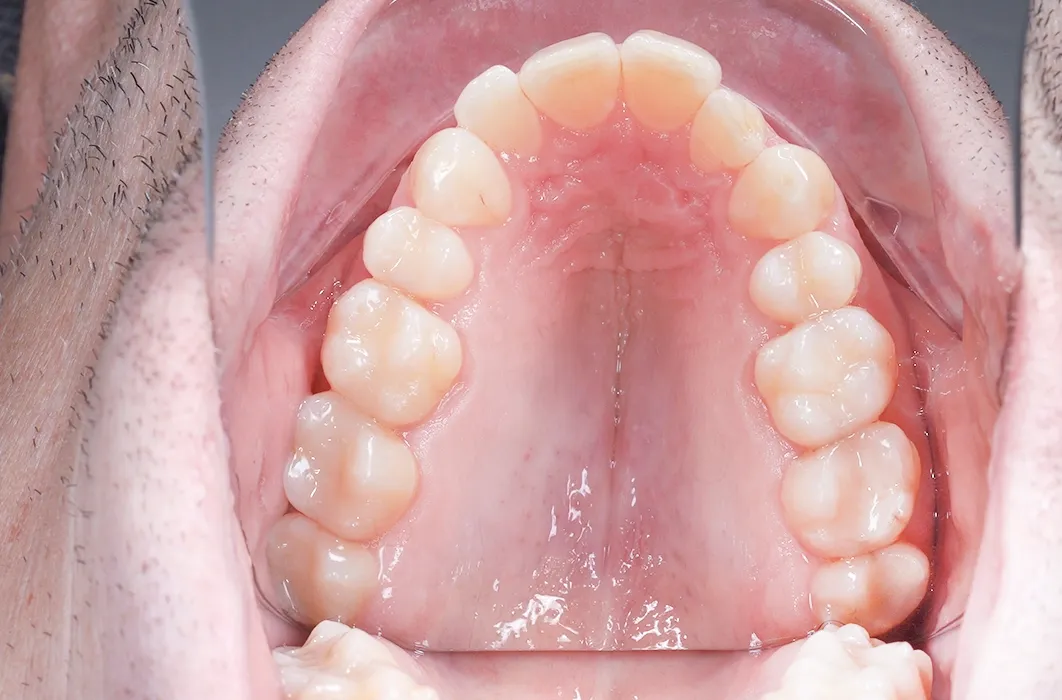

By rebuilding the shape and structure of each tooth with composite restorations, Mr C’s molars were reinforced and his bite was maintained.

The results

Mr C’s teeth went from being worn, darkened, and at risk of breakdown to looking healthier, stronger, and natural. The resin restorations not only gave his smile a more uniform appearance, but also reinforced surfaces to reduce the risk of future decay and damage.